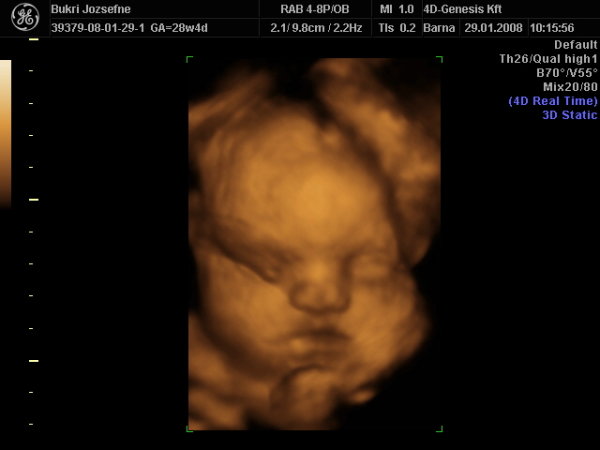

Tudom nagyon rég jártam erre de van a pici puncisunkról képeim és megszeretném nektek mutatni bár nagyon nem akarta megmutatni a lába közét ismét teljesen a 4d-n de nem adta fel a szonográfus és 40 perc után a kicsi lány terpesztett egyet és így már biztire tudjuk a nemét is.A neve még kérdéses !

Milyen hamar eltelt az idő nemsokára babázni fogsz és igaz kixcsit messze van nekem az április de én is nem sokára. Kép lányunk Kép lányunk Ez már bizonyíték!!!